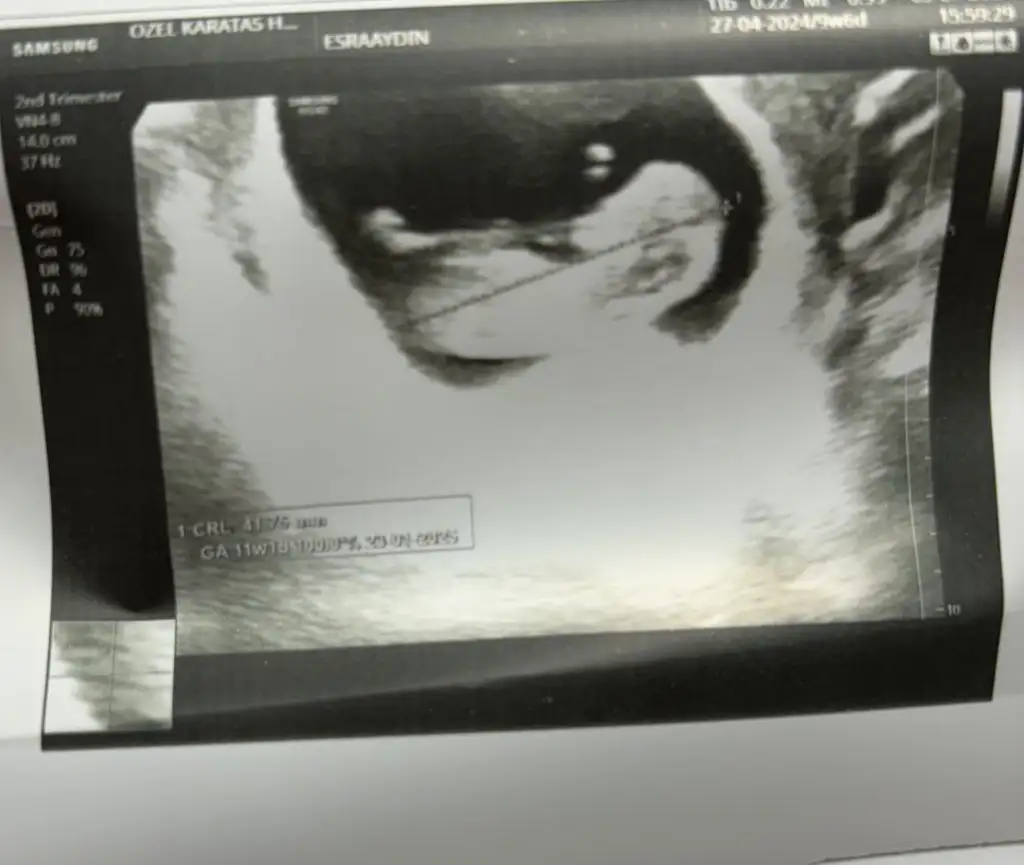

Yok be kuzum daha 10 haftalığız yarın kontrole gideceğim ama daha bi 3 hafta sonra anca belli olur tahminen bakalım yarınki ultrasonla az da olsa belki anlaşılırCinsiyet belli oldu mu kız

Doğuma girerken bana dua etcen bak unutma sakın kocana kaynana herkese söyle hatırlatsınlar sanaYok be kuzum daha 10 haftalığız yarın kontrole gideceğim ama daha bi 3 hafta sonra anca belli olur tahminen bakalım yarınki ultrasonla az da olsa belki anlaşılır![]()

Benimkinde bi tahminde bulunurmusunjz 9+5 karından ultrasonSizin beybi de küçük:)

ErkekBenimkinde bi tahminde bulunurmusunjz 9+5 karından ultrason